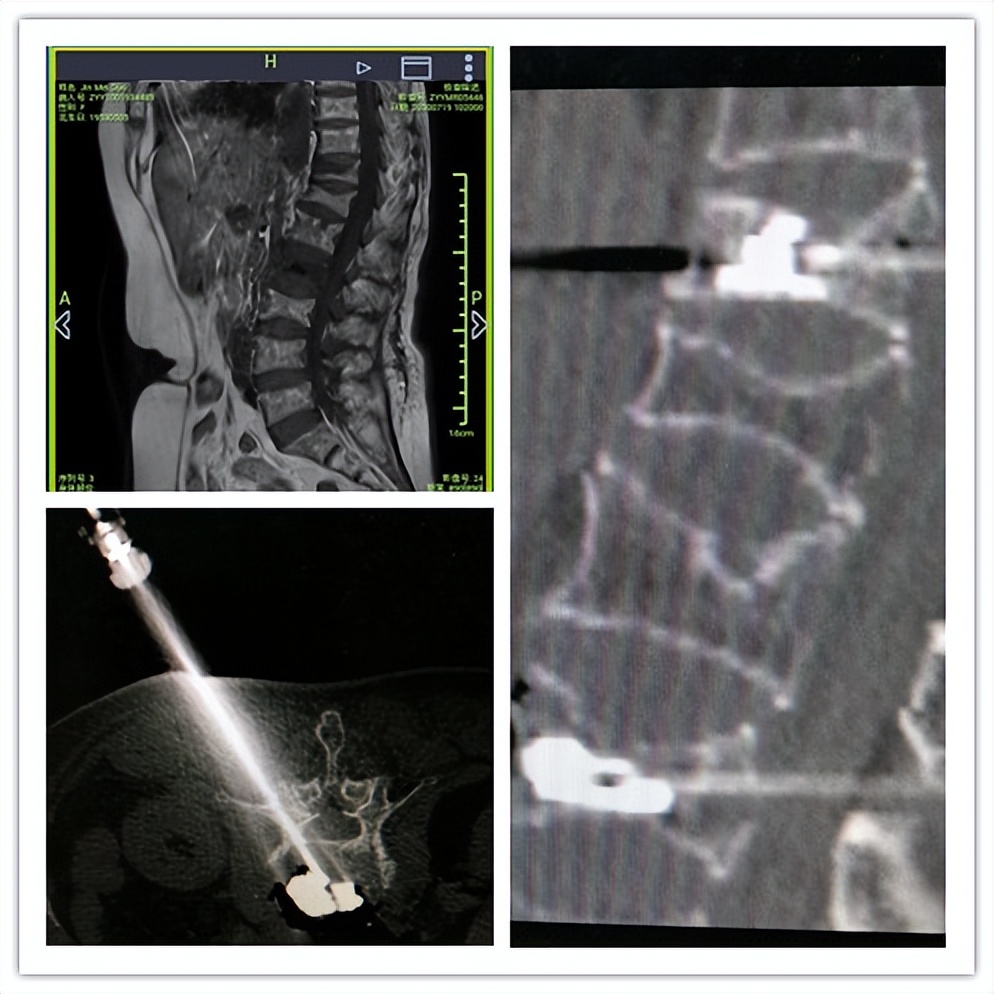

(腰椎间盘突出症:椎间孔镜下腰椎间盘髓核摘除)

(老年骨质疏松引起的胸腰椎骨折:经皮穿刺椎体成形)